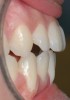

Fig 17. Lateral view of same patient showing the root prominence.

Figure 17

A 19-year-old female complaining of gingival recession in the lower right central incisor presented to the authors’ clinic 5 years after completion of orthodontic treatment. The clinical evaluation showed Miller Class II GR accompanied by gingival inflammation (Figure 14). Two years later, despite conservative periodontal treatment, the GR had worsened (Figure 15). The occlusal view shows the presence of a fixed lingual retainer and a significant labial displacement of the root of the affected incisor (Figure 16 and Figure 17). At this stage, orthodontic treatment was considered. The patient was referred for CBCT, which showed no labial bone coverage of the root but 2.5 mm lingual bone thickness at 8 mm distance from the CEJ (Figure 18). After 6 months of orthodontic treatment with fixed appliances (Figure 19), the B-L inclination of the affected tooth was corrected (Figure 20). The frontal clinical view shows narrowing of the GR (Figure 21). Surgical coverage of the exposed root was subsequently performed by connective tissue graft (Figure 22). A long-term stable and esthetic result was achieved (Figure 23).